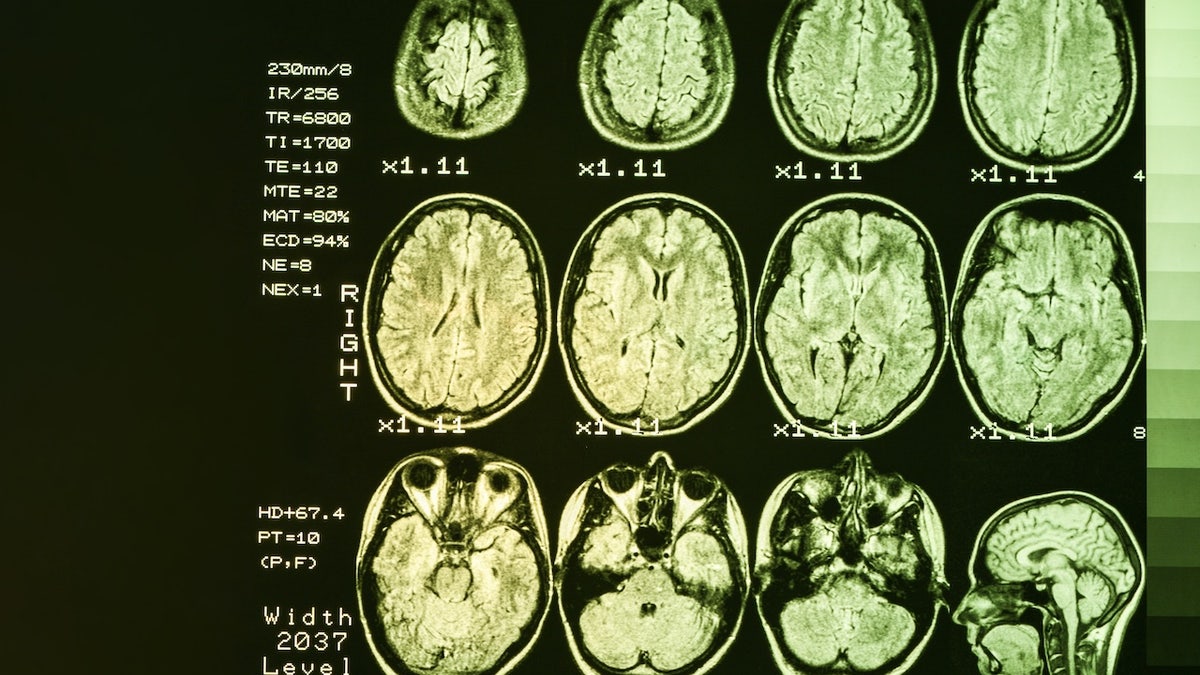

Scientists may have discovered the first therapy for Huntington’s disease, a brain disorder that until now has had no effective treatments. (iStock)